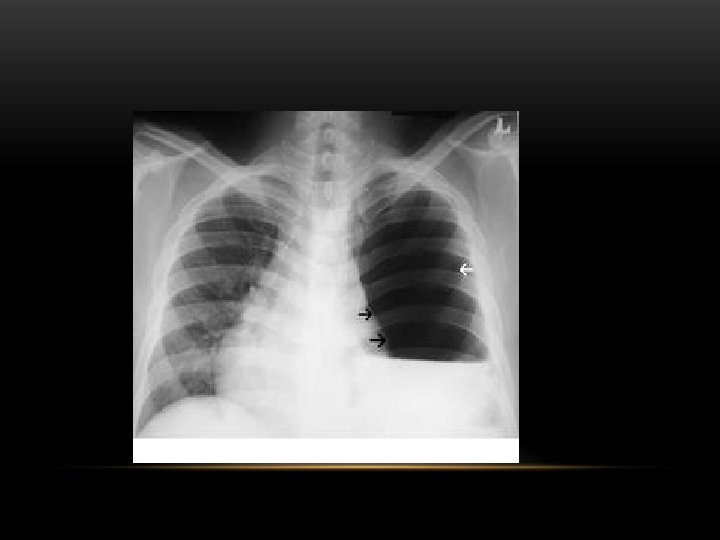

Pneumothorax • No vascular markings on right • No shift of mediastinum to left • Atelectasis right lung • Increased haziness on left: Diversion of entire cardiac output • Small fluid level near costophrenic angle: Hydro pneumothorax

Tension Pneumothorax • No vascular markings on right • Shift of mediastinum to left • Atelectasis right lung • Increased haziness on left: Diversion of entire cardiac output

Spontaneous Pneumothorax • Air in pleural space • Lung margin • "Normal lungs": Note the radiolucency of atelectatic lung is the same as the opposite lung